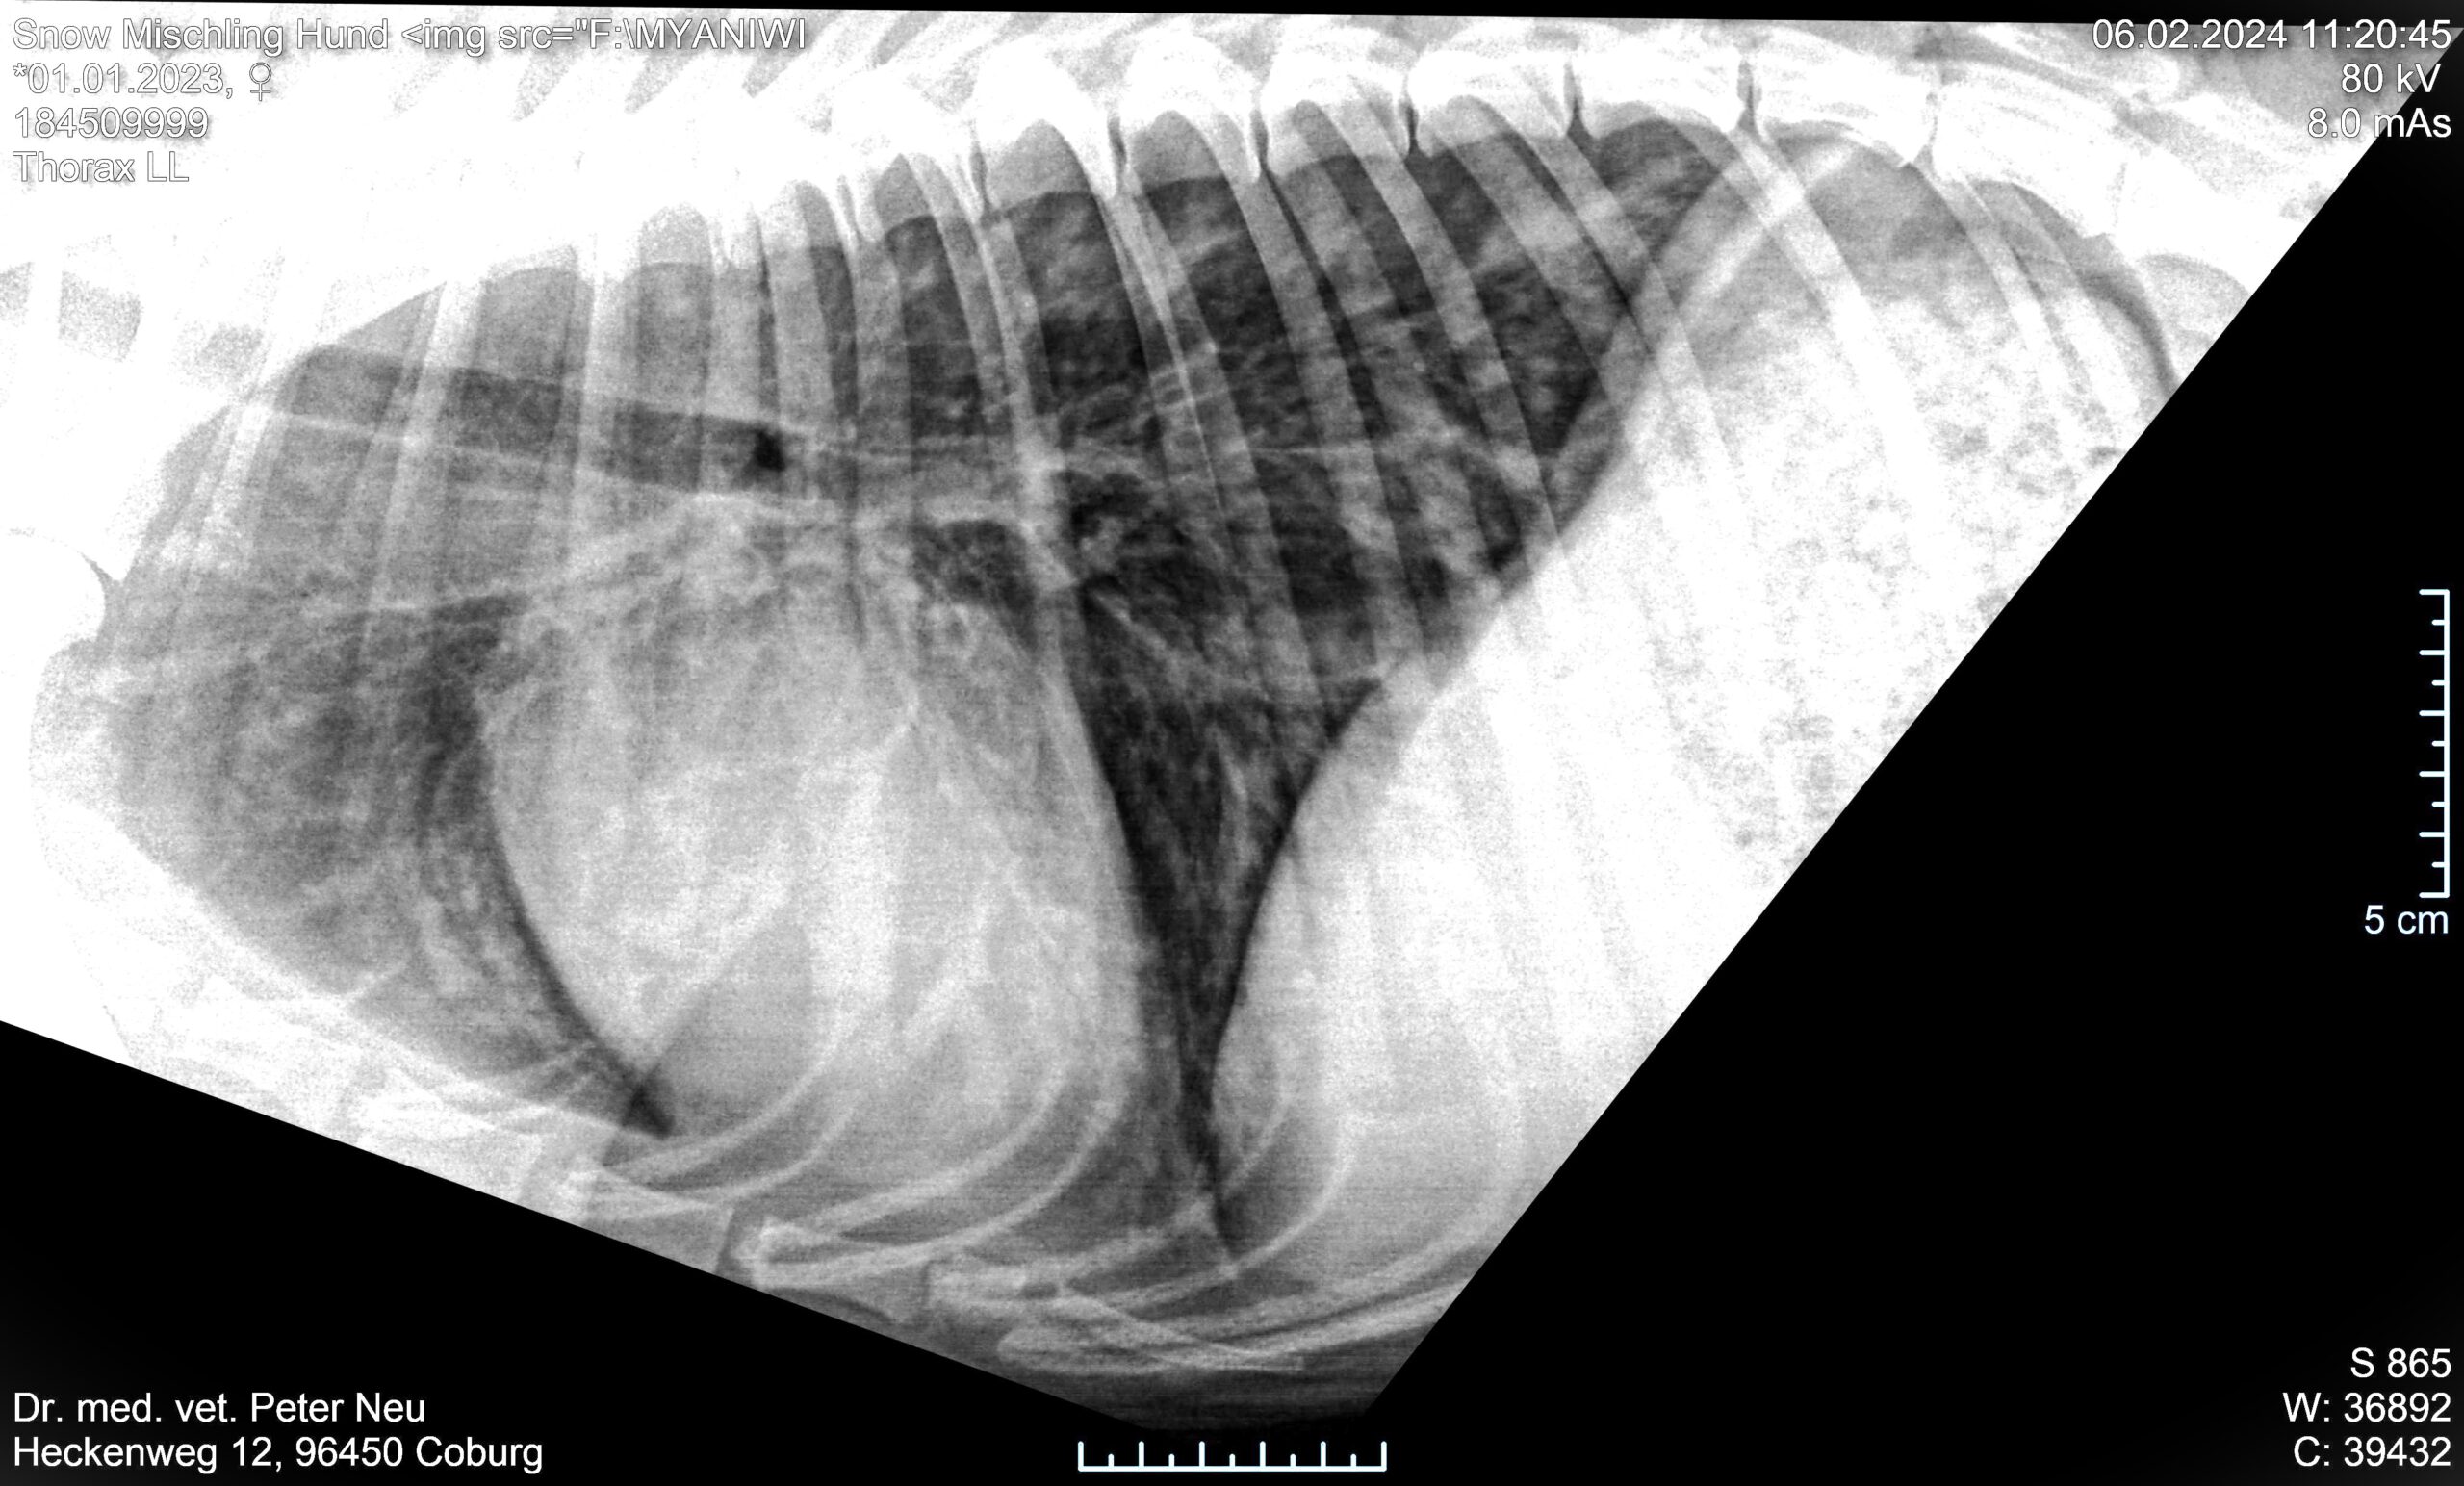

Im Röntgen sieht man deutlich Verschattungen der Lungengefässe mit einem dezentralen, peripheretn Muster. Die Herzsilhouhette erscheint normal. Im Blutbild gibt es eine bedeutende regerative Anämie.